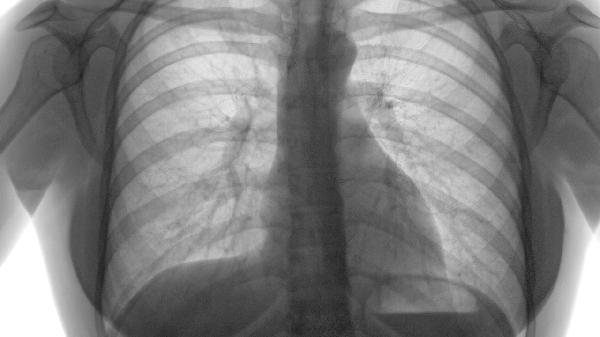

肺气肿严重时可能引发脸肿脚肿,主要与右心衰竭、低氧血症、二氧化碳潴留、静脉回流受阻及继发性醛固酮增多有关。

长期肺气肿导致肺动脉高压,增加右心负荷,最终引发右心衰竭。右心衰竭时,体循环静脉回流受阻,血液淤积在组织间隙,表现为下肢水肿,严重时可波及面部。治疗需针对原发病,如使用支气管扩张剂沙丁胺醇、异丙托溴铵、氧疗改善肺功能,同时配合利尿剂呋塞米、螺内酯减轻水肿。

肺气肿患者肺泡换气功能下降,血氧饱和度降低,长期缺氧导致血管通透性增加,水分渗出至组织间隙形成水肿。需通过长期家庭氧疗每日≥15小时纠正缺氧,必要时使用无创通气设备,并监测血氧水平。

二氧化碳分压升高引起呼吸性酸中毒,导致肾小管重吸收钠离子增多,水钠潴留加重水肿。需通过机械通气改善通气功能,药物可选用乙酰唑胺促进二氧化碳排出,限制钠盐摄入每日≤3g。

胸腔内压力增高压迫上腔静脉,影响头面部静脉回流;同时腹压升高阻碍下肢静脉回流。睡眠时抬高床头30度,穿戴医用弹力袜压力20-30mmHg,避免久坐久站。

慢性缺氧刺激肾素-血管紧张素系统,醛固酮分泌增加导致水钠潴留。可选用醛固酮拮抗剂依普利酮,配合高钾饮食香蕉、菠菜平衡电解质。

肺气肿患者日常需保证每日热量摄入30-35kcal/kg,蛋白质1.2-1.5g/kg,避免高碳水化合物饮食加重二氧化碳生成。进行缩唇呼吸训练每日3组,每组10分钟及上肢抗阻运动弹力带训练每周3次,睡眠时采用侧卧位减轻膈肌压迫。定期监测体重变化,24小时内增长≥1kg需警惕水肿加重。